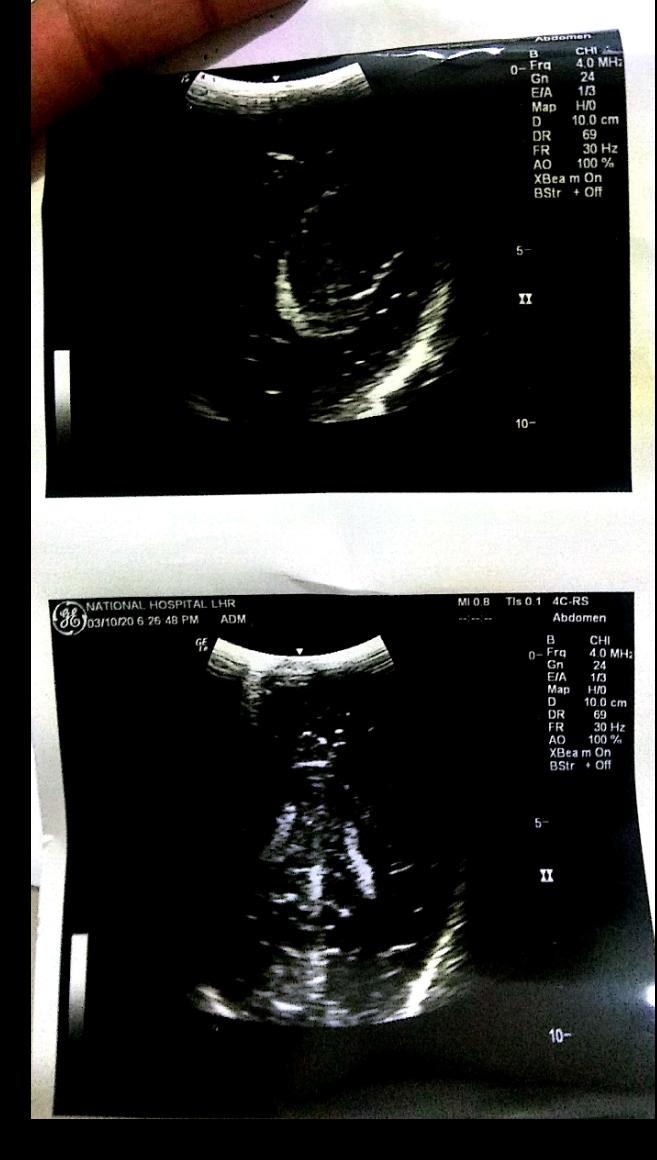

Few days back i have posted about my niece vaccine, she had her vaccine and was having bleeding for 3days after that, she went to doc and they said to just do icing. After 3 to 4days in morning she did vomit and motion, after feeding she slept as normal, but later didn't respond, they immediately took her to hospital 'isko sans lene mai prib horhe hai' doc said konsi sanz isko koi sans nahi arhe, and shifted to Icu ventilator.. Docs have no hope. We want second opinion attaching her reports kindly give your opinion asap, i have more pics but can attach only 5

kindly provide more reports and CT scan if available.

she seems to have bleeding disorder which causes prolonged bleeding and probable bleed in her brain

that made her unconcious